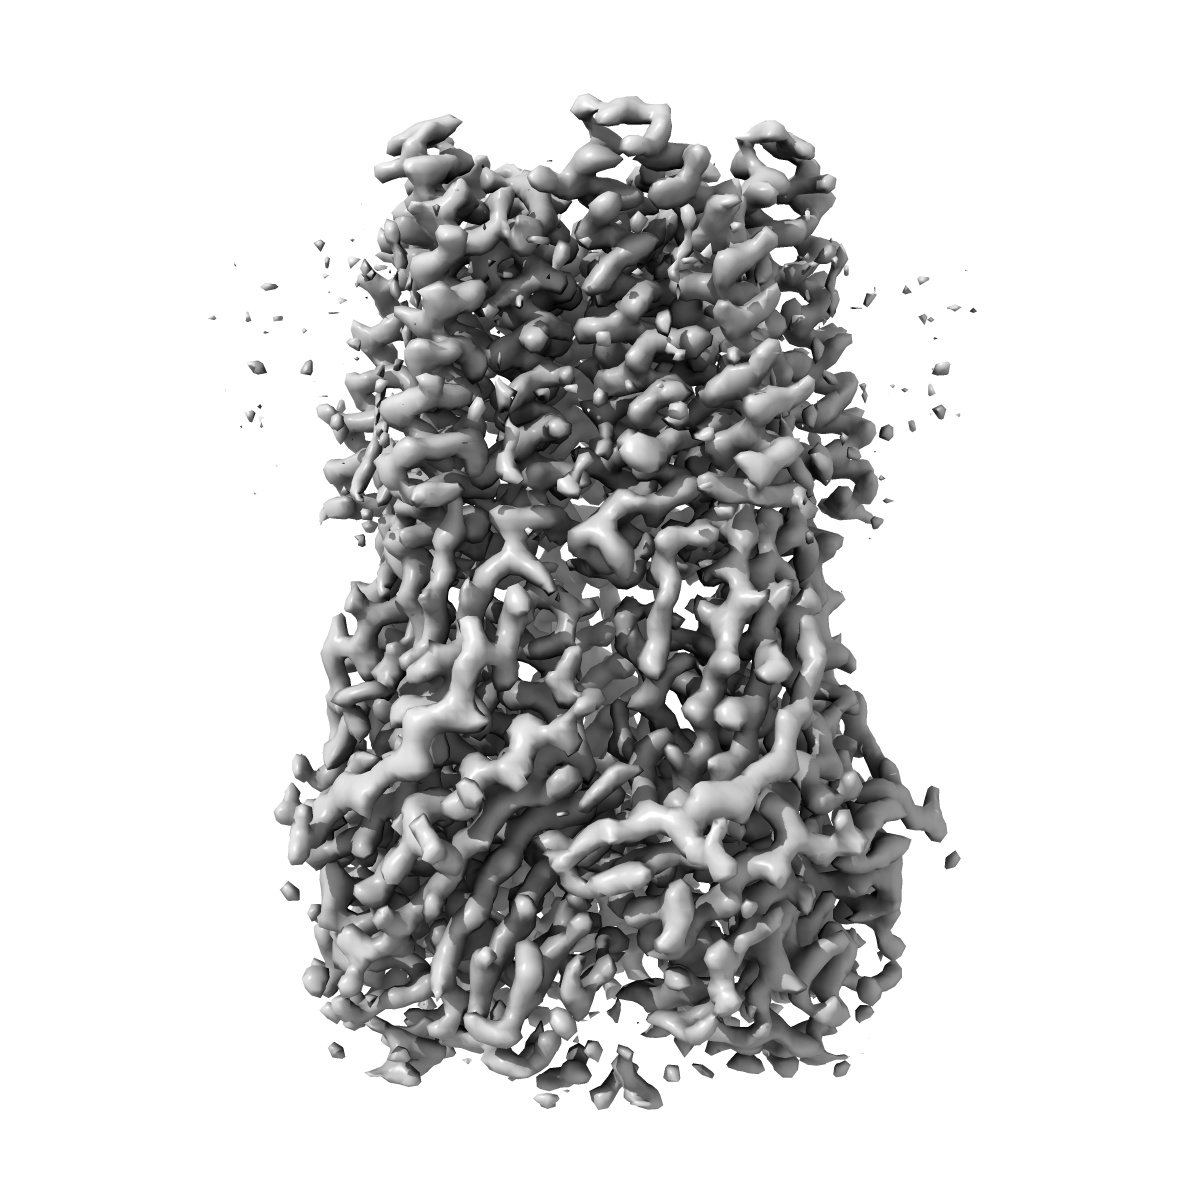

EMD-16067

GABA-A receptor a5 homomer - a5V3 - RO7015738

Single-particle3.38 Å

Sample: GABA-A a5 subunit of homopentamer complex called a5V3